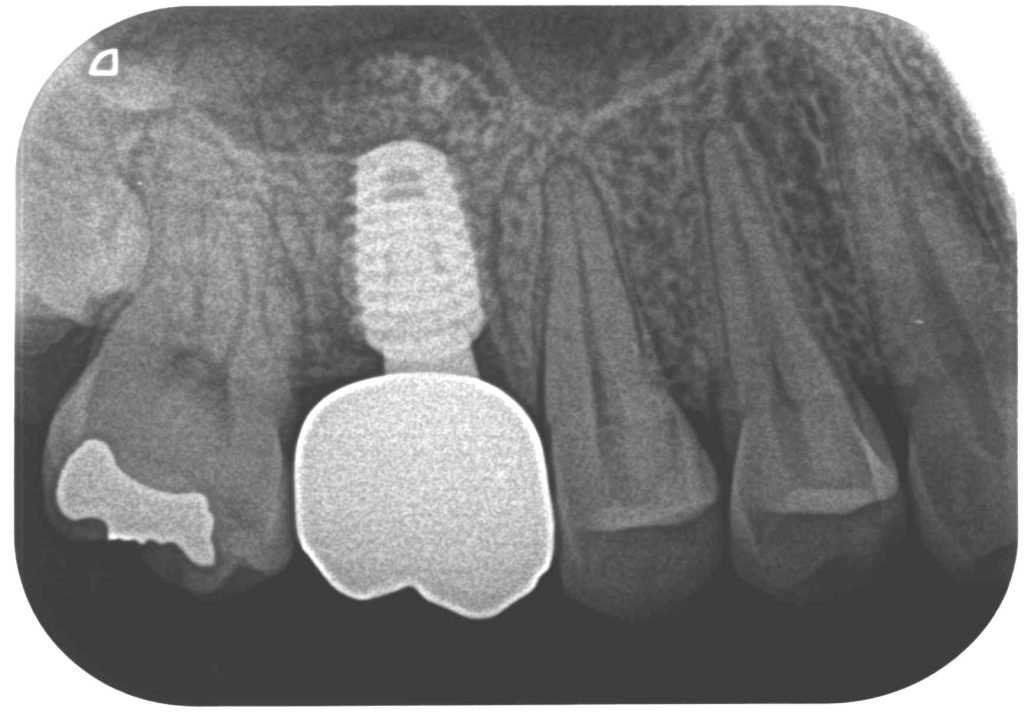

症例130代 女性 歯根破折にて右上6番を抜歯

治療前

治療後

ブリッジ・義歯・インプラントの選択肢を提案。

両隣在歯を削り、より負担のかかるブリッジや義歯は選択肢にはなく、両隣在歯を守るインプラントを選択。

骨高不足の為、ソケットリフト(上顎洞洞底膜挙上術)を適用。

オペ後、骨との密着値も良く、約2ヶ月後にはジルコニアを装着し終了。

リスクとしては外科的侵襲がある。デメリットは、保険外診療の為、経済的負担がある。

費用 64万(税込)(オペ・仮歯・最終補綴物まで含む)